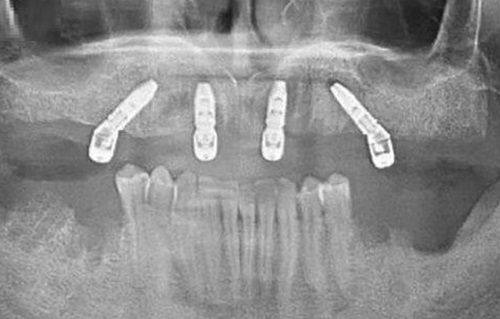

在深圳合诺口腔,赵中华医生擅长镶牙种植牙、牙齿美白、牙齿矫正、牙体牙髓、牙周病治疗等项目。在镶牙种植牙方面,他熟练掌握精良口腔种植体系,能进行全口单颗种植,尤其擅长all - on - 4、即刻种植等技术,能让患者在较短时间内修复牙齿功能。牙齿美白项目中,他能根据患者的牙齿情况制定个性化的美白方案,让患者拥有洁白亮丽的牙齿。牙齿矫正方面,他擅长传统直丝弓矫正、舌侧隐形矫正、无托槽隐形矫正以及儿童早期矫正等多种矫正方式,能有效解决各种牙齿不齐问题,实现牙列 - 牙弓形态 - 咬颌关系 - 颞颌关节 - 咬肌发育 - 唇齿笑线 - 笑容颜面的整体协调美。

实例一:在深圳合诺口腔,一位中老年患者因牙齿缺失多年,生活受到较大影响。赵中华医生为他进行了详细的口腔检查后,制定了all - on - 4种植方案。手术过程非常顺利,患者当天就能咀嚼食物。患者评价说:“赵医生技术真是太厉害了,我一直担心种牙会特别痛苦,没想到这么轻松就完成了。现在我的牙齿就像真牙一样,吃饭也香了,生活质量大大提高了。而且赵医生特别耐心,术前给我详细解释了手术过程和注意事项,让我心里特别踏实。”